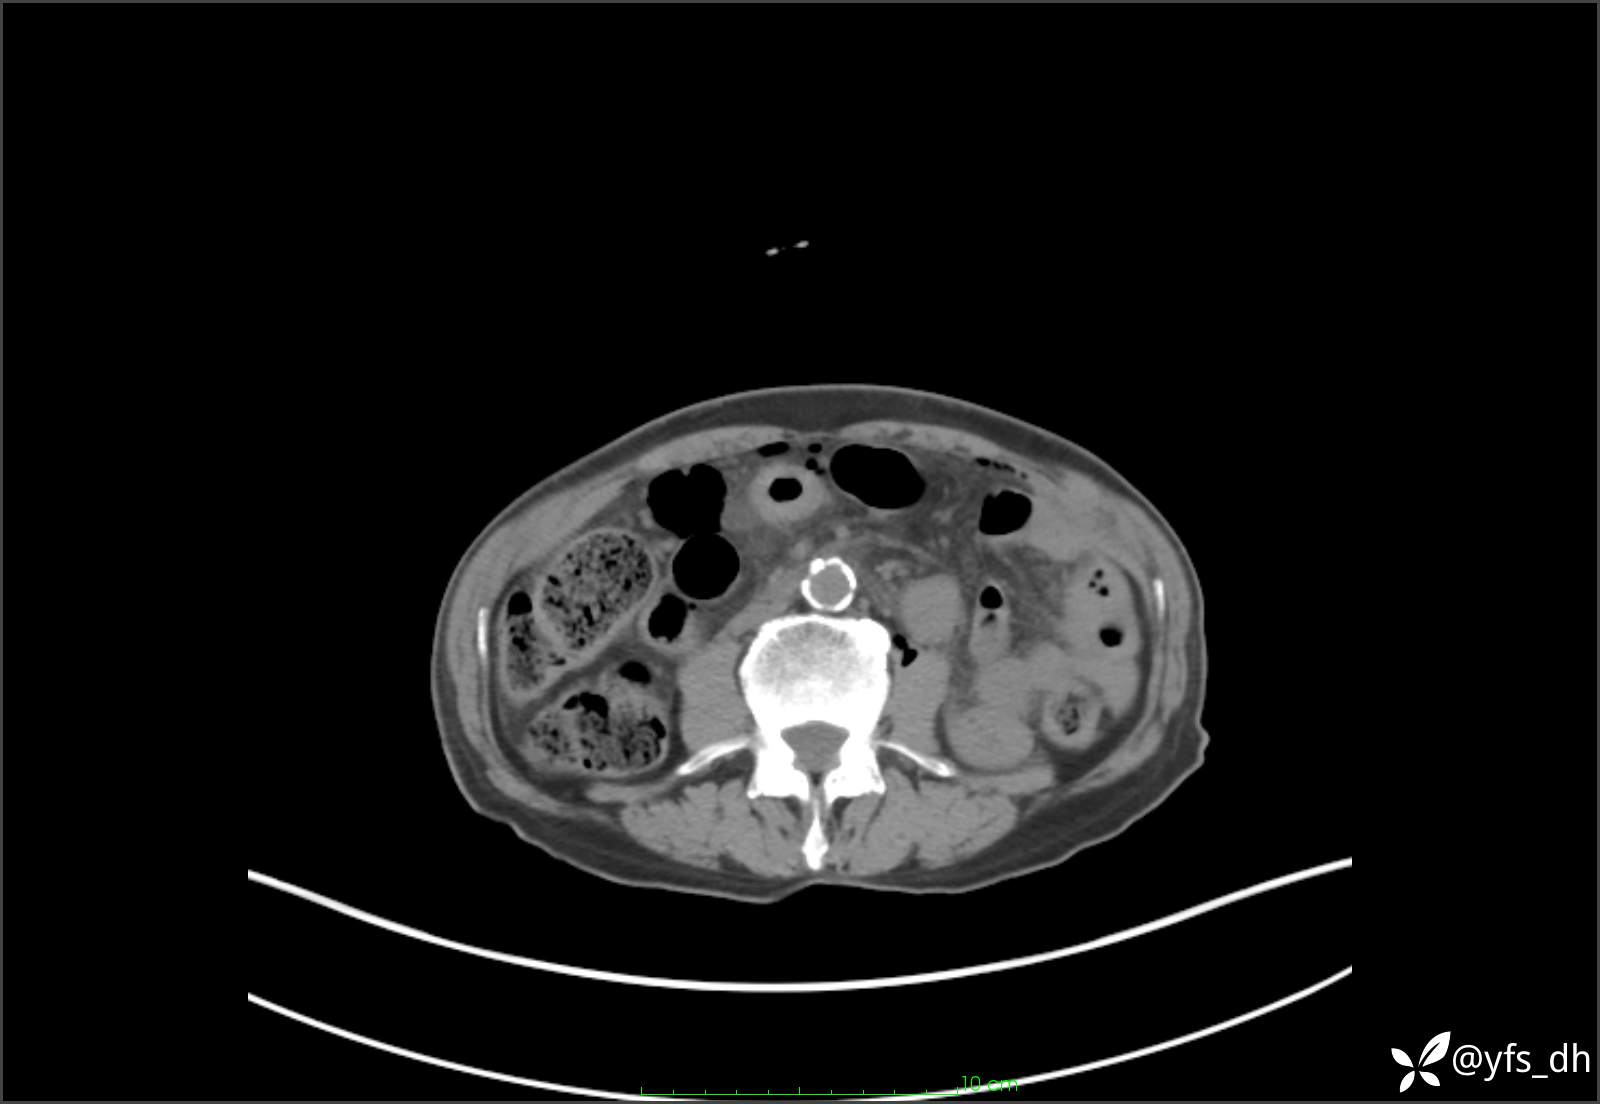

1.简要病史:患者4天前突发上腹部疼痛不适,但可以忍受。3小时前饭后突然加重,不能忍受后就诊。

2.简要手术记录:术中见腹盆腔大量肠液及粪便,乙状结肠中下段见一约3cm的破口。